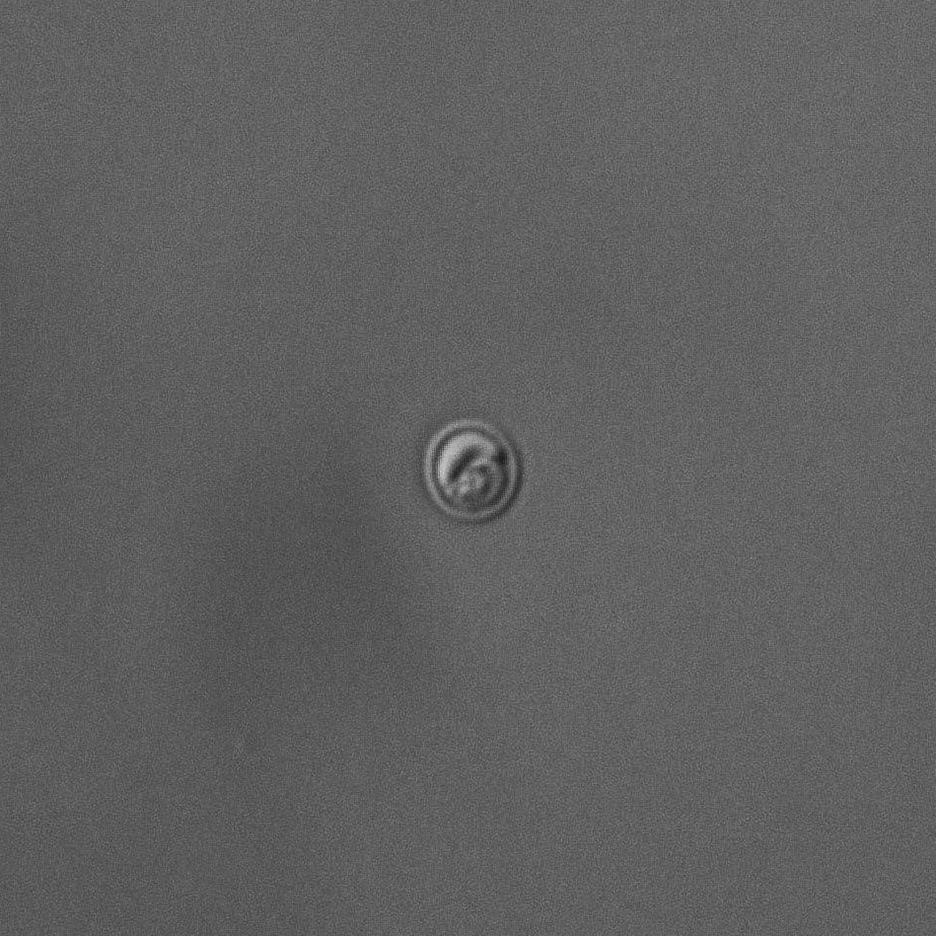

クリプトスポリジウムは、微分干渉装置付きの蛍光顕微鏡※2でしか観察できません。最初に青緑色に蛍光染色した対象を蛍光観察し、オーシストの存在を確認。青緑色に光る丸いものがあれば、クリプトスポリジウムの可能性がありますが断定はできません。この状態では殻の外側しか観察できず、藻類などが光っている可能性もあるからです。そこで、微分干渉観察に切り換えて殻の内部構造を確認します。微分干渉観察は、無色透明な物体を明暗のコントラストで捉えます。明瞭な像を得るために、コンデンサーレンズ(集光レンズ)の位置やコントラストの調整などの微妙な操作が必要。「この微妙な操作がクリプトスポリジウムの検査が“難しい”と言われる最大の理由だと思います」と、馬場さんはおっしゃっていました。微分干渉観察で、厚い殻の中にバナナが四本あるような構造を確認できれば、ようやくクリプトスポリジウムの存在が陽性であると判定できるのです。

微分干渉観察で捉えたクリプトスポリジウム

画像提供:前澤工業㈱ 環境事業本部

環境R&D推進室 分析センター